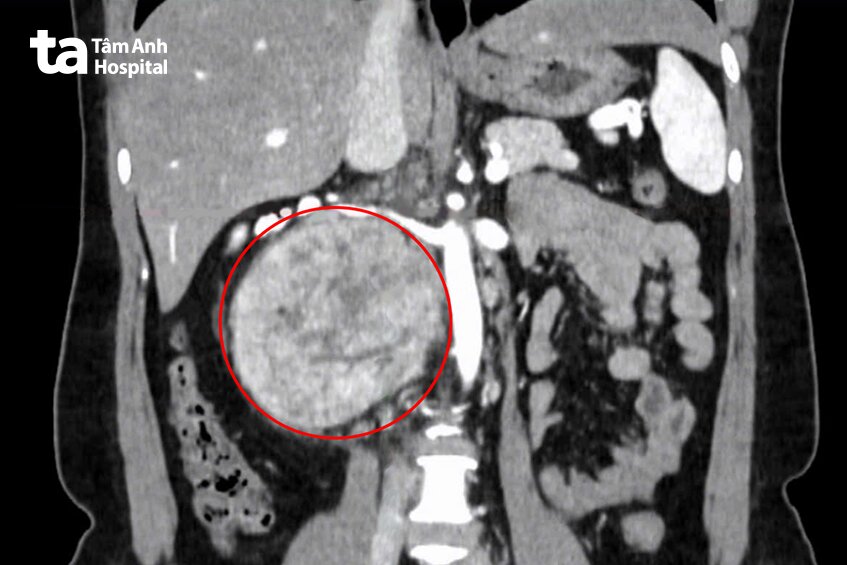

2 tuần trước, chị Ngà đến Bệnh viện Đa khoa Tâm Anh TP.HCM khám sức khỏe tổng quát, kết quả chụp cắt lớp vi tính (CT Scan) vùng bụng phát hiện một khối u rất lớn ở vùng sau phúc mạc – là những khối u bất thường xuất hiện giữa khoang ổ bụng và cột sống lưng, thường phát sinh từ mô, thần kinh, tế bào mầm hoặc các nang sau phúc mạc.

“Khối u rất lớn, kích thước 12 cm nằm sau tĩnh mạch chủ, cạnh động mạch và hai tĩnh mạch thận, gây chèn ép các cơ quan lân cận, chúng tôi phải tiến hành mổ mở để lấy trọn khối u một cách tốt nhất cho người bệnh”, TS.BS Nguyễn Hoàng Đức, Trưởng khoa Tiết niệu, Trung tâm Tiết niệu – Thận học – Nam khoa, Bệnh viện Đa khoa Tâm Anh TP.HCM, cho biết.